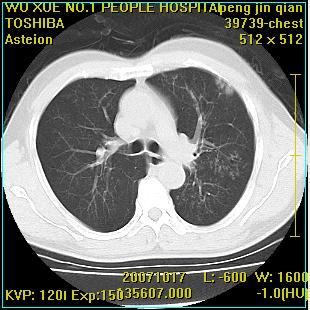

标题: CT10148:男,56岁,咳血。 [打印本页]

标题: CT10148:男,56岁,咳血。

左肺上叶尖后段较大团块影,边缘光滑,内见不规则裂隙样空洞,周围明显见细小结节及渗出,与肺门方向结构紊乱,另:左上叶尖段外侧 舌叶内侧 右上叶尖段及下叶背段均见片状致密影。考虑:继发性肺结核伴空洞形成!

左上肺后壁空洞,内壁不规则,可见壁结节;左上叶尖段外侧 舌叶内侧 右上叶尖段及下叶背段均见片状致密影。考虑:左肺肺癌并两肺继发性肺结核?

左肺上叶尖后段较大团块影,边缘光滑,内见不规则裂隙样空洞,周围明显见细小结节及渗出,与肺门方向结构紊乱,另:左上叶尖段外侧 舌叶内侧 右上叶尖段及下叶背段均见片状致密影。考虑:继发性肺结核伴空洞形成!建议进一步检查,除外肺癌